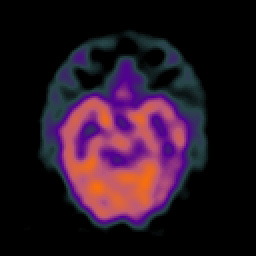

SPECT TC Study #1 -- Slice #20

[Home][Help][Clinical][Tour 1][Tour 2][Tour 3] Slice 20